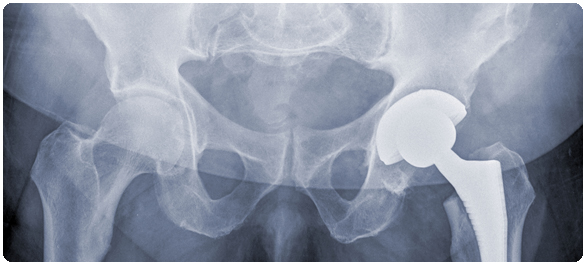

สะโพกหัก โรคฮิตของคนแก่ (ตอนที่ 5 และตอนจบ)

ส่วนการรักษาโรคกระดูกพรุนนั้น ผศ.นพ.ธนินนิตย์ กล่าวว่า ต้องประกอบด้วยการปรับปรุงการใช้ชีวิตประจำวัน (Lifestyle modifications) ผู้ป่วยทุกคนควรออกกำลังกายที่ให้ร่างกายมีการรับน้ำหนักต่อกระดูก เช่น การเดิน การวิ่ง ร่วมกับการฝึกความแข็งแรงของกล้ามเนื้อ ส่วนในรายที่มีปัญหาในการเคลื่อนไหวควรส่งต่อให้นักกายภาพบำบัดเพื่อทำการฟื้นฟูสมรรถภาพของร่างกาย

สำหรับการใช้ยารักษาโรคกระดูกพรุน ผศ.นพ.ธนินนิตย์ กล่าวต่อว่า ปัจจุบันยาที่ใช้ในการรักษาโรคกระดูกพรุนมี 2 กลุ่ม คือ 1) ยาที่กระตุ้นการสร้างมวลกระดูกขึ้นมาใหม่ซึ่งใช้ด้วยการฉีดเข้าใต้ผิวหนังทุกวันวันละ 1 ครั้ง ต่อเนื่องกันนาน 2 ปี เหมาะสมกับผู้ป่วยที่เป็นโรคกระดูกพรุนชนิดรุนแรงร่วมกับการเกิดกระดูกหักหลายตำแหน่ง และ 2) ยายับยั้งการทำลายกระดูกซึ่งมี 2 รูปแบบ ทั้งชนิดรับประทาน และชนิดฉีดเข้าเส้นเลือด หรือฉีดเข้าชั้นใต้ผิวหนัง

ในท้ายสุด ผศ.นพ.ธนินนิตย์ กล่าวสรุปว่า ความสำเร็จของการรักษาโรคกระดูกพรุนขึ้นอยู่กับการปรับเปลี่ยนวิถีการดำเนินชีวิต การรับประทานอาหาร แคลเซียม วิตามินดี และการใช้ยาอย่างต่อเนื่องและสม่ำเสมอ รวมทั้งป้องกันไม่ให้หกล้ม ทั้งนี้ผู้ป่วยโรคกระดูกพรุนไม่ควรก้มเก็บของเพราะจะเพิ่มโอกาสการยุบตัวของกระดูกสันหลังด้วย